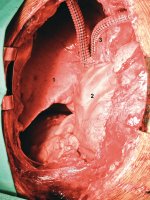

Thymus - Resektion

Abbildung 3: Intraoperativer Situs nach Resektion des Thymus, obere Bilobektomie (1) (Lungenunterlappen) wegen pulmonaler Infiltration, Resektion des N. phrenicus, Perikardresektion und Resektion der Bifurkation der beiden Venae anonymae; Rekonstruktion des Perikards mittels Vicrylnetz (2), Gefäßrekonstruktion mittels YDacron- Prothese (3). Nach zusätzlicher adjuvanter Radiochemotherapie ist der Patient nach 5 Jahren immer noch rezidivfrei.